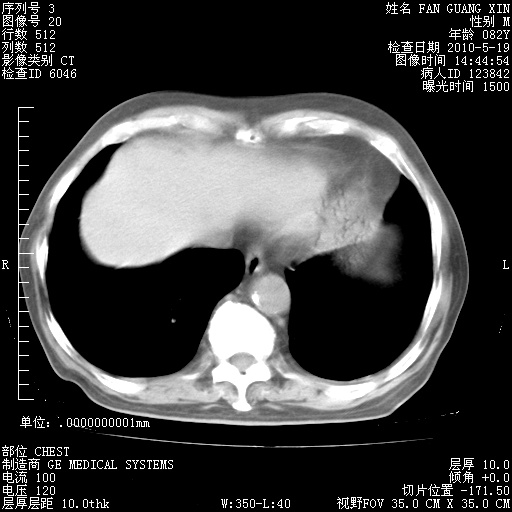

治疗3周后的肺部CT纵隔窗

从胸部影像学来看,的确有好转。至于目前为何发热不甚清楚?除了发热还有其他症状如有无喀痰,痰呈丝状吗?等等。尽量搜寻有无致发热其它可能原因?真菌?其它?如果的确无其他致发热的原因,考虑将甲强龙调至60-80mg bid/日。免疫全套基本无异常,考虑多系特发性肺间质纤维化